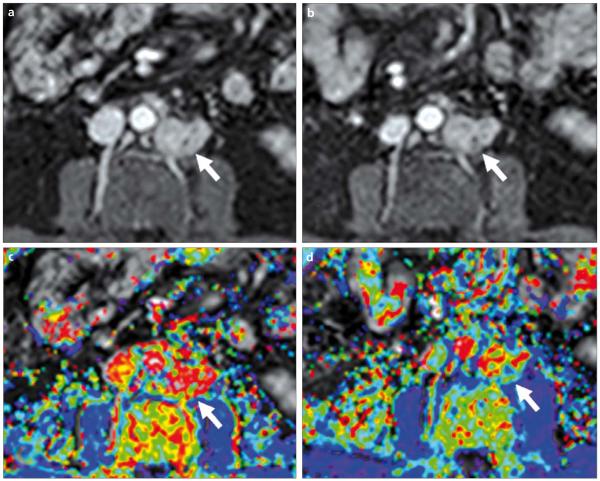

a-d. A 57-year-old male with metastatic prostate cancer to the retroperitoneal lymph nodes. DCE-MR images were obtained before (a, c) and after (b, d) anti-angiogenic therapy. T1W images (upper row) reveal subtle changes within the lesion. Ktrans color maps (lower row) show significant reduction in values, consistent with response to anti-angiogenic therapy (arrows).